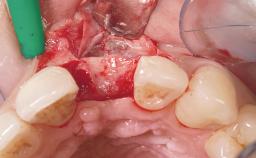

Late Flapless Placement of an Implant in a Maxillary Left Central Incisor Site

A 39-year-old male patient presented with a chief complaint of discomfort and gingival discoloration around his maxillary left central incisor. He was in good general health and was a non-smoker. His past dental history was significant because of the traumatic fracture of tooth 21 in a sporting accident at age 13. Initial dental treatment included endodontic therapy and a full-coverage restoration. The patient became symptomatic 5 years later, when structural failure of the tooth resulted in the dislodgment of the crown. Endodontic retreatment, apical surgery, and post-and-core restoration were performed.

Bone Augmentation Horizontal|Staged

Augmentation Materials Xenogenous|Membrane

Bone Volume Deficient horizontally, requiring prior grafting